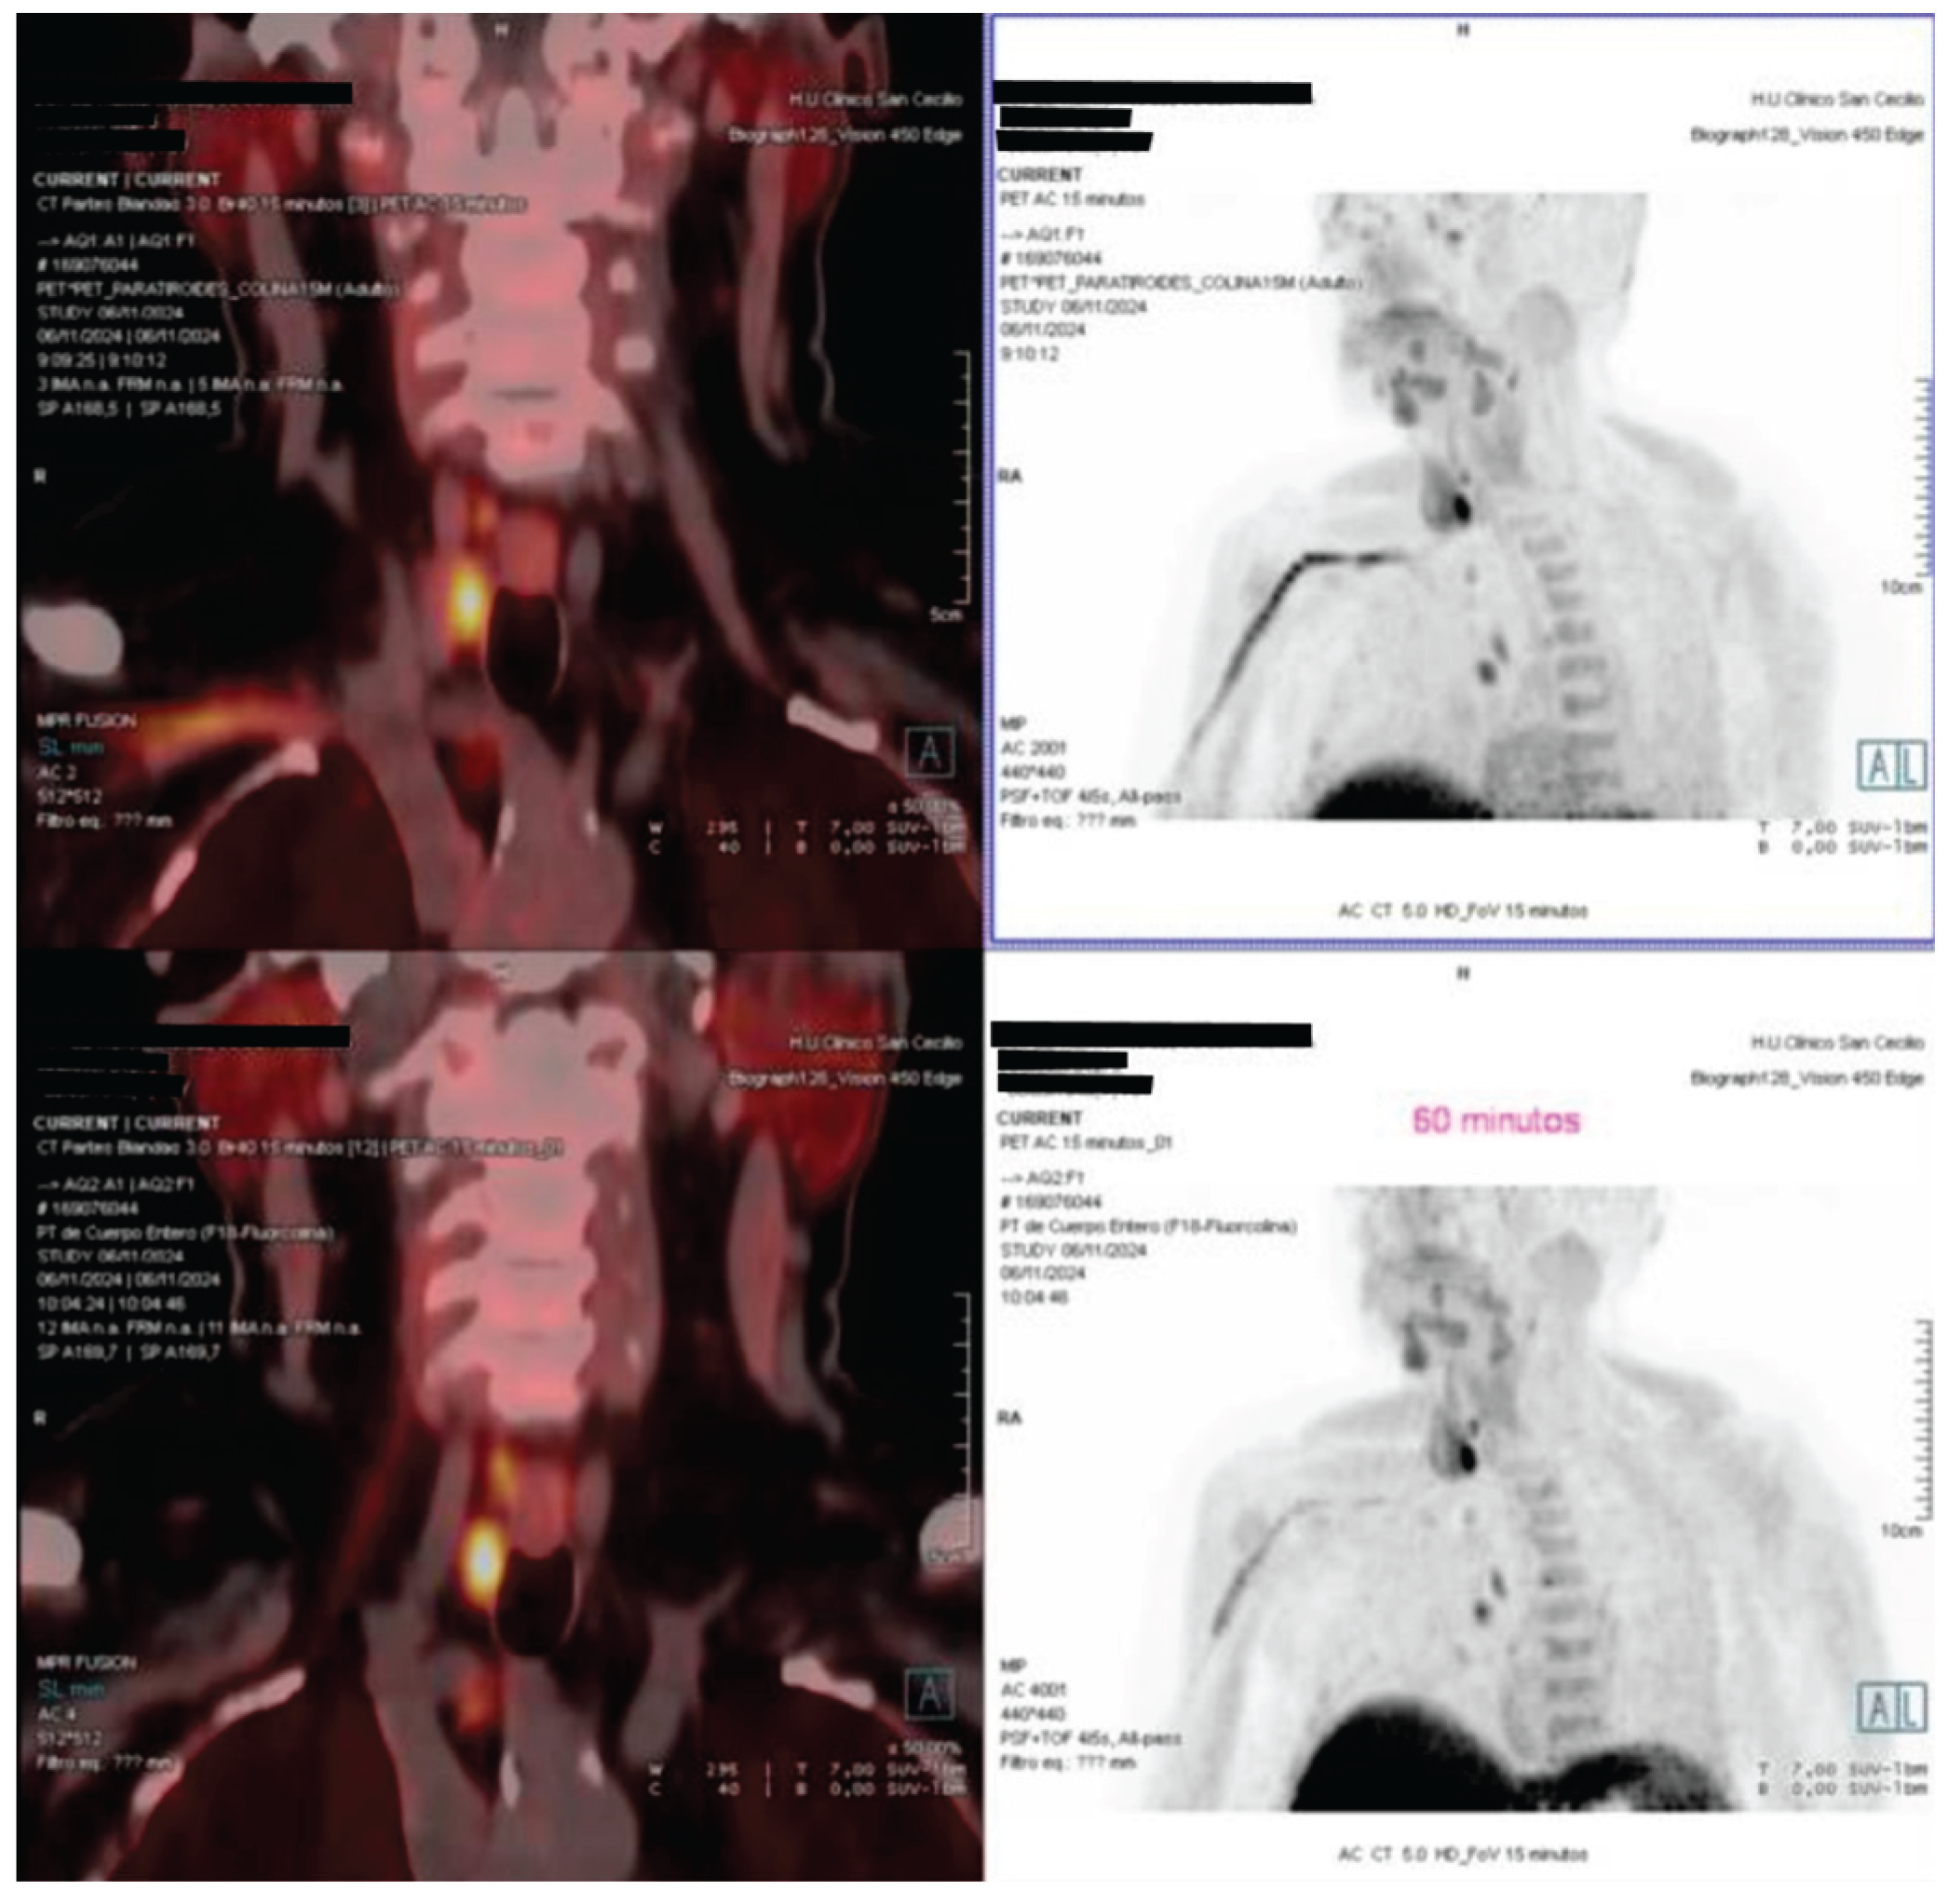

An 18F-fluorocholine PET-CT (18F-choline PET-CT) scan performed in November 2024 identified two right parathyroid adenomas, located in the upper and lower poles. The patient did not report renal colic, falls or new fractures. At the most recent follow-up, a diagnosis of PHPT was confirmed, characterized by hypercalcemia, persistent hypophosphatemia, elevated PTH and FGF-23 levels and absence of hypercalciuria or overt hyperphosphaturia.

Figure 1. Fused coronal and axial images (left) and anterior projection MIP sections (right) identify two areas of focal increased uptake in the right cervical region. The uptake corresponds to a posterosuperior nodular lesion and an inferoposterior nodular lesion adjacent to the right thyroid lobe, findings consistent with double right parathyroid adenomas (superior and inferior).